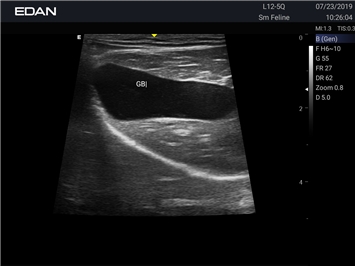

EDAN Acclarix AX2 VET представляет собой специализированную ветеринарную ультразвуковую систему, сочетающую высокую производительность с доступной ценой. Благодаря продуманной конструкции и передовым технологиям, система обеспечивает качественную диагностику животных различных видов.

Революционная платформа визуализации:

• Высокое разрешение для детальной диагностики

• Улучшенная визуализация глубоко расположенных органов

• Технология адаптивной визуализации тканей:

• Непрерывная автоматическая оптимизация изображения

• Адаптация к особенностям анатомии разных видов животных

• Повышенная точность исследований

• Предустановленные протоколы для различных видов животных